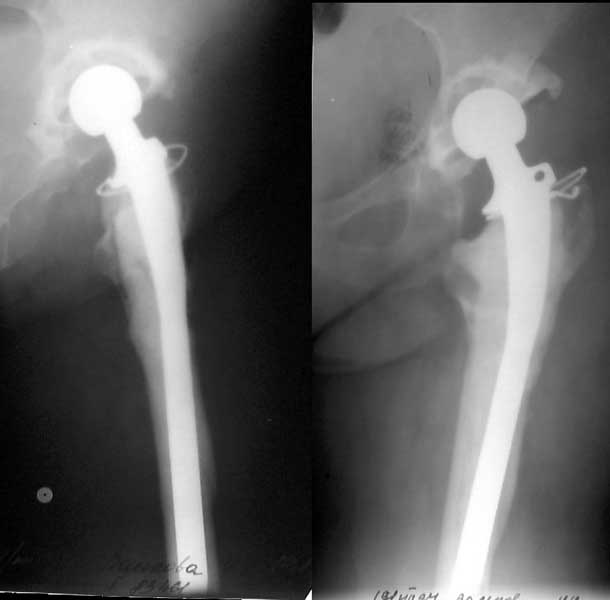

Женщине 1948 г.р. в 1995 г. по поводу левостороннего коксартроза III было выполнено эндопротезирование протезом "Феникс". В 1997 - ревизионное протезирование цементным протезом Beznoska (снимок приложен). В конце июля-начале августа появились боли и подвижность ниже ножки протеза - на снимке нестабильность ножки и перелом диафиза.Если ревизионный протез с удлиненной ножкой, пригодной для остеосинтеза бедра, будет недоступен, какой вариант действий предпочесть? Пока мысли удалить протез, цемент, сделать костную пластику верхнего конца бедра и остеосинтез стержнем, а после сращения перелома бедра - удаление стержня и обычное ревизионное протезирование.

Здесь свежий снимок, уже с переломом.